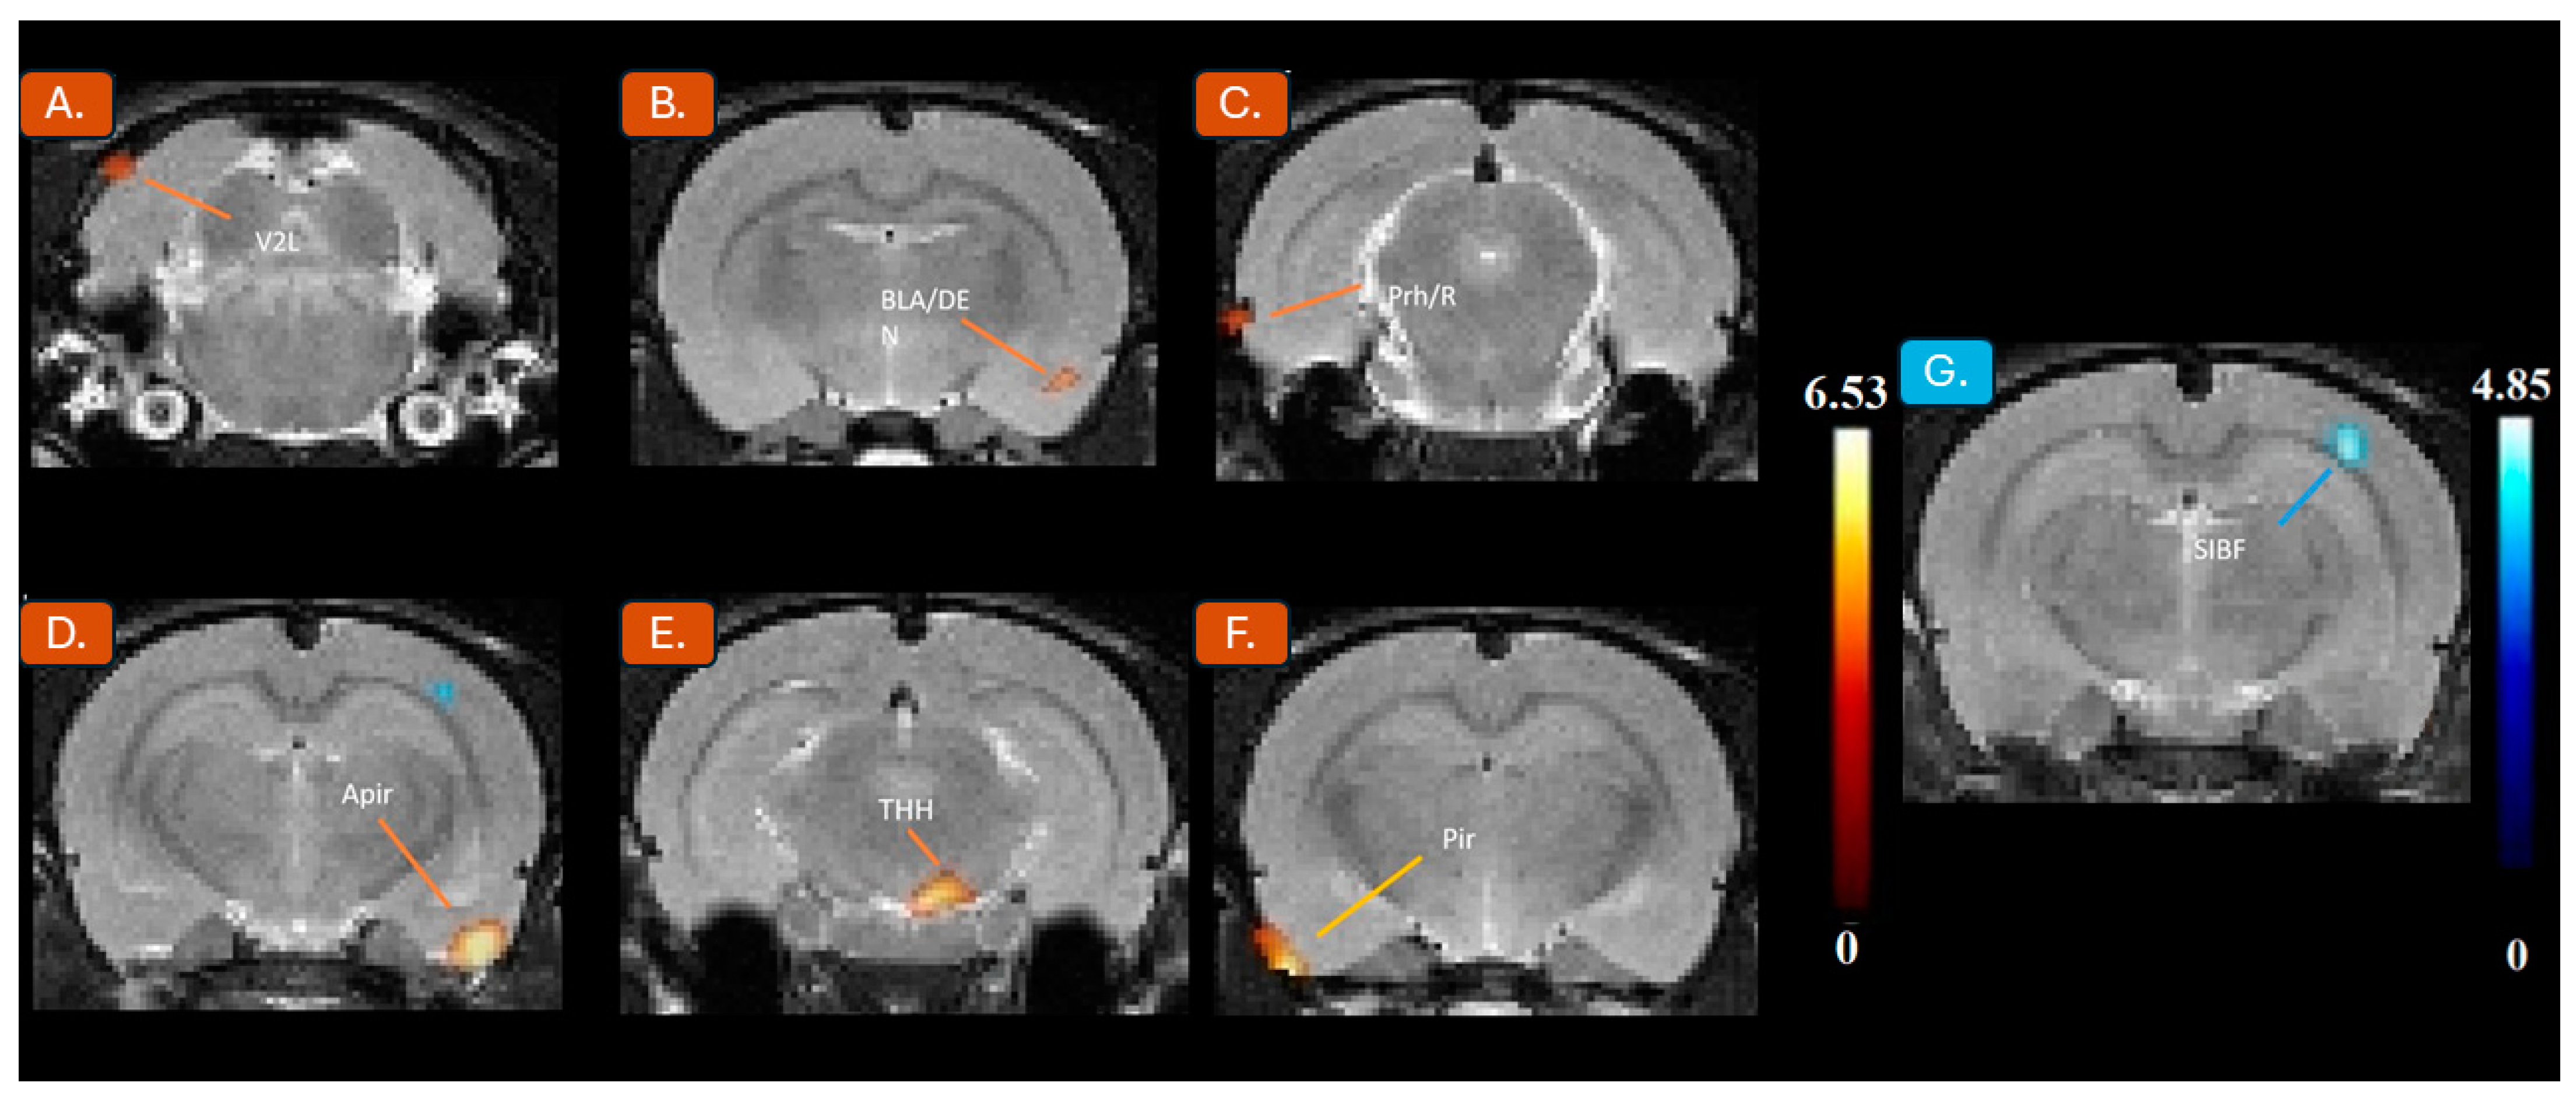

| Brain Region (s) | Activated or Inhibited | ML (mm) | DV (mm) | AP (mm) | t Value | z-Score | KE |

|---|---|---|---|---|---|---|---|

| Primary somatosensory cortex (SIBF) | Inhibited | 44 | 26 | −44 | 4.85 | 3.32 | 99 |

| Piriform cortex (Pir) | Activated | −58 | 104 | −28 | 6.53 | 3.87 | 94 |

| Amygdalopiriform transition (Apir) | Activated | 56 | 100 | −42 | 6.39 | 3.83 | 244 |

| Trigeminothalamic tract (TTH) | Activated | 10 | 84 | −60 | 5.57 | 3.58 | 178 |

| Basolateral amygdaloid nucleus, dorsal (BLA/DEN) | Activated | 52 | 90 | −20 | 4.56 | 3.2 | 67 |